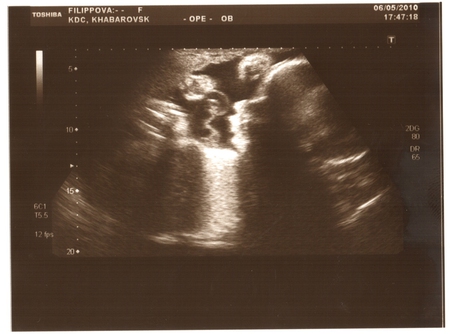

6 мая ходили с мужем на третье УЗИ. Так как там фильмов не снимают и так далее, взяли с собой камеру и снимали все....теперь смотрим и улыбаемся, как наш сыночек там двигается и ручкой голову чешет:)

Результаты все отличные!!! Ура! Плацента 1 степени зрелости- однородная, воды в норме, пуповина ничего не обвивает, ребенок лежит правильно, головой вниз.

Еще он личико прятал ручками то нос почешет то глазки прикроет..и натурально голову чесал:)) так смешно:)..еще губками двигал как будто чавкает:) мило так:)

фотка получилась не очень...но все равно выложу...(там справа голова и хорошо видны носик и губки)